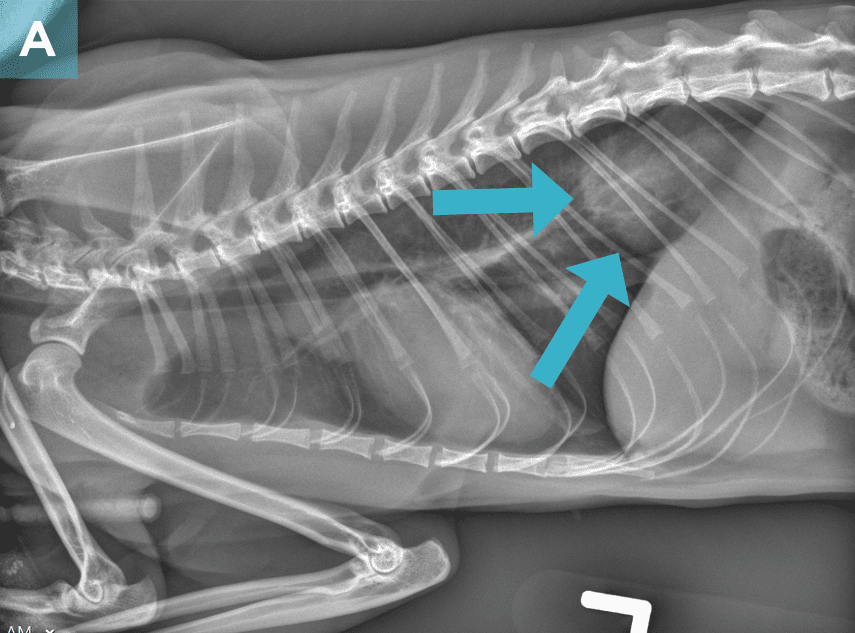

Diagnostic Imaging

On survey thoracic radiographs, the heart and lungs were normal. A soft tissue opacity in broad-based contact with the diaphragm was noted in the caudal thorax (FIGURE 2), and the intra-abdominal portion of the stomach was shifted slightly cranially and to the left; findings were consistent with a hiatal hernia. The cat was anesthetized for computed tomography (CT) of the head and possible surgery.